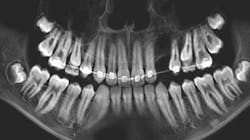

A 14-year-old female presented to her general dentist complaining of pain in the right posterior mandible and mobility of tooth no. 31. Her medical history was otherwise unremarkable. A panoramic radiograph revealed a large, multilocular radiolucent lesion within the entire ramus and posterior body of the right mandible. Tooth no. 32 was within the lesion. Cortical expansion in the area of the lesion was notable. All adjacent teeth were vital. A panoramic radiograph taken at the completion of orthodontic treatment 18 months previously showed no evidence of the lesion.

A 13-year-old male was noted by his orthodontist to have an expanding radiolucency encompassing impacted tooth no. 11. The patient was without complaint, and his medical history was otherwise unremarkable. A CT scan revealed a multilocular radiolucency extending from the maxillary midline to the area of the left permanent second molar and expanding into the left maxillary sinus. Cortical expansion in the area of the lesion was notable and all adjacent teeth were vital.